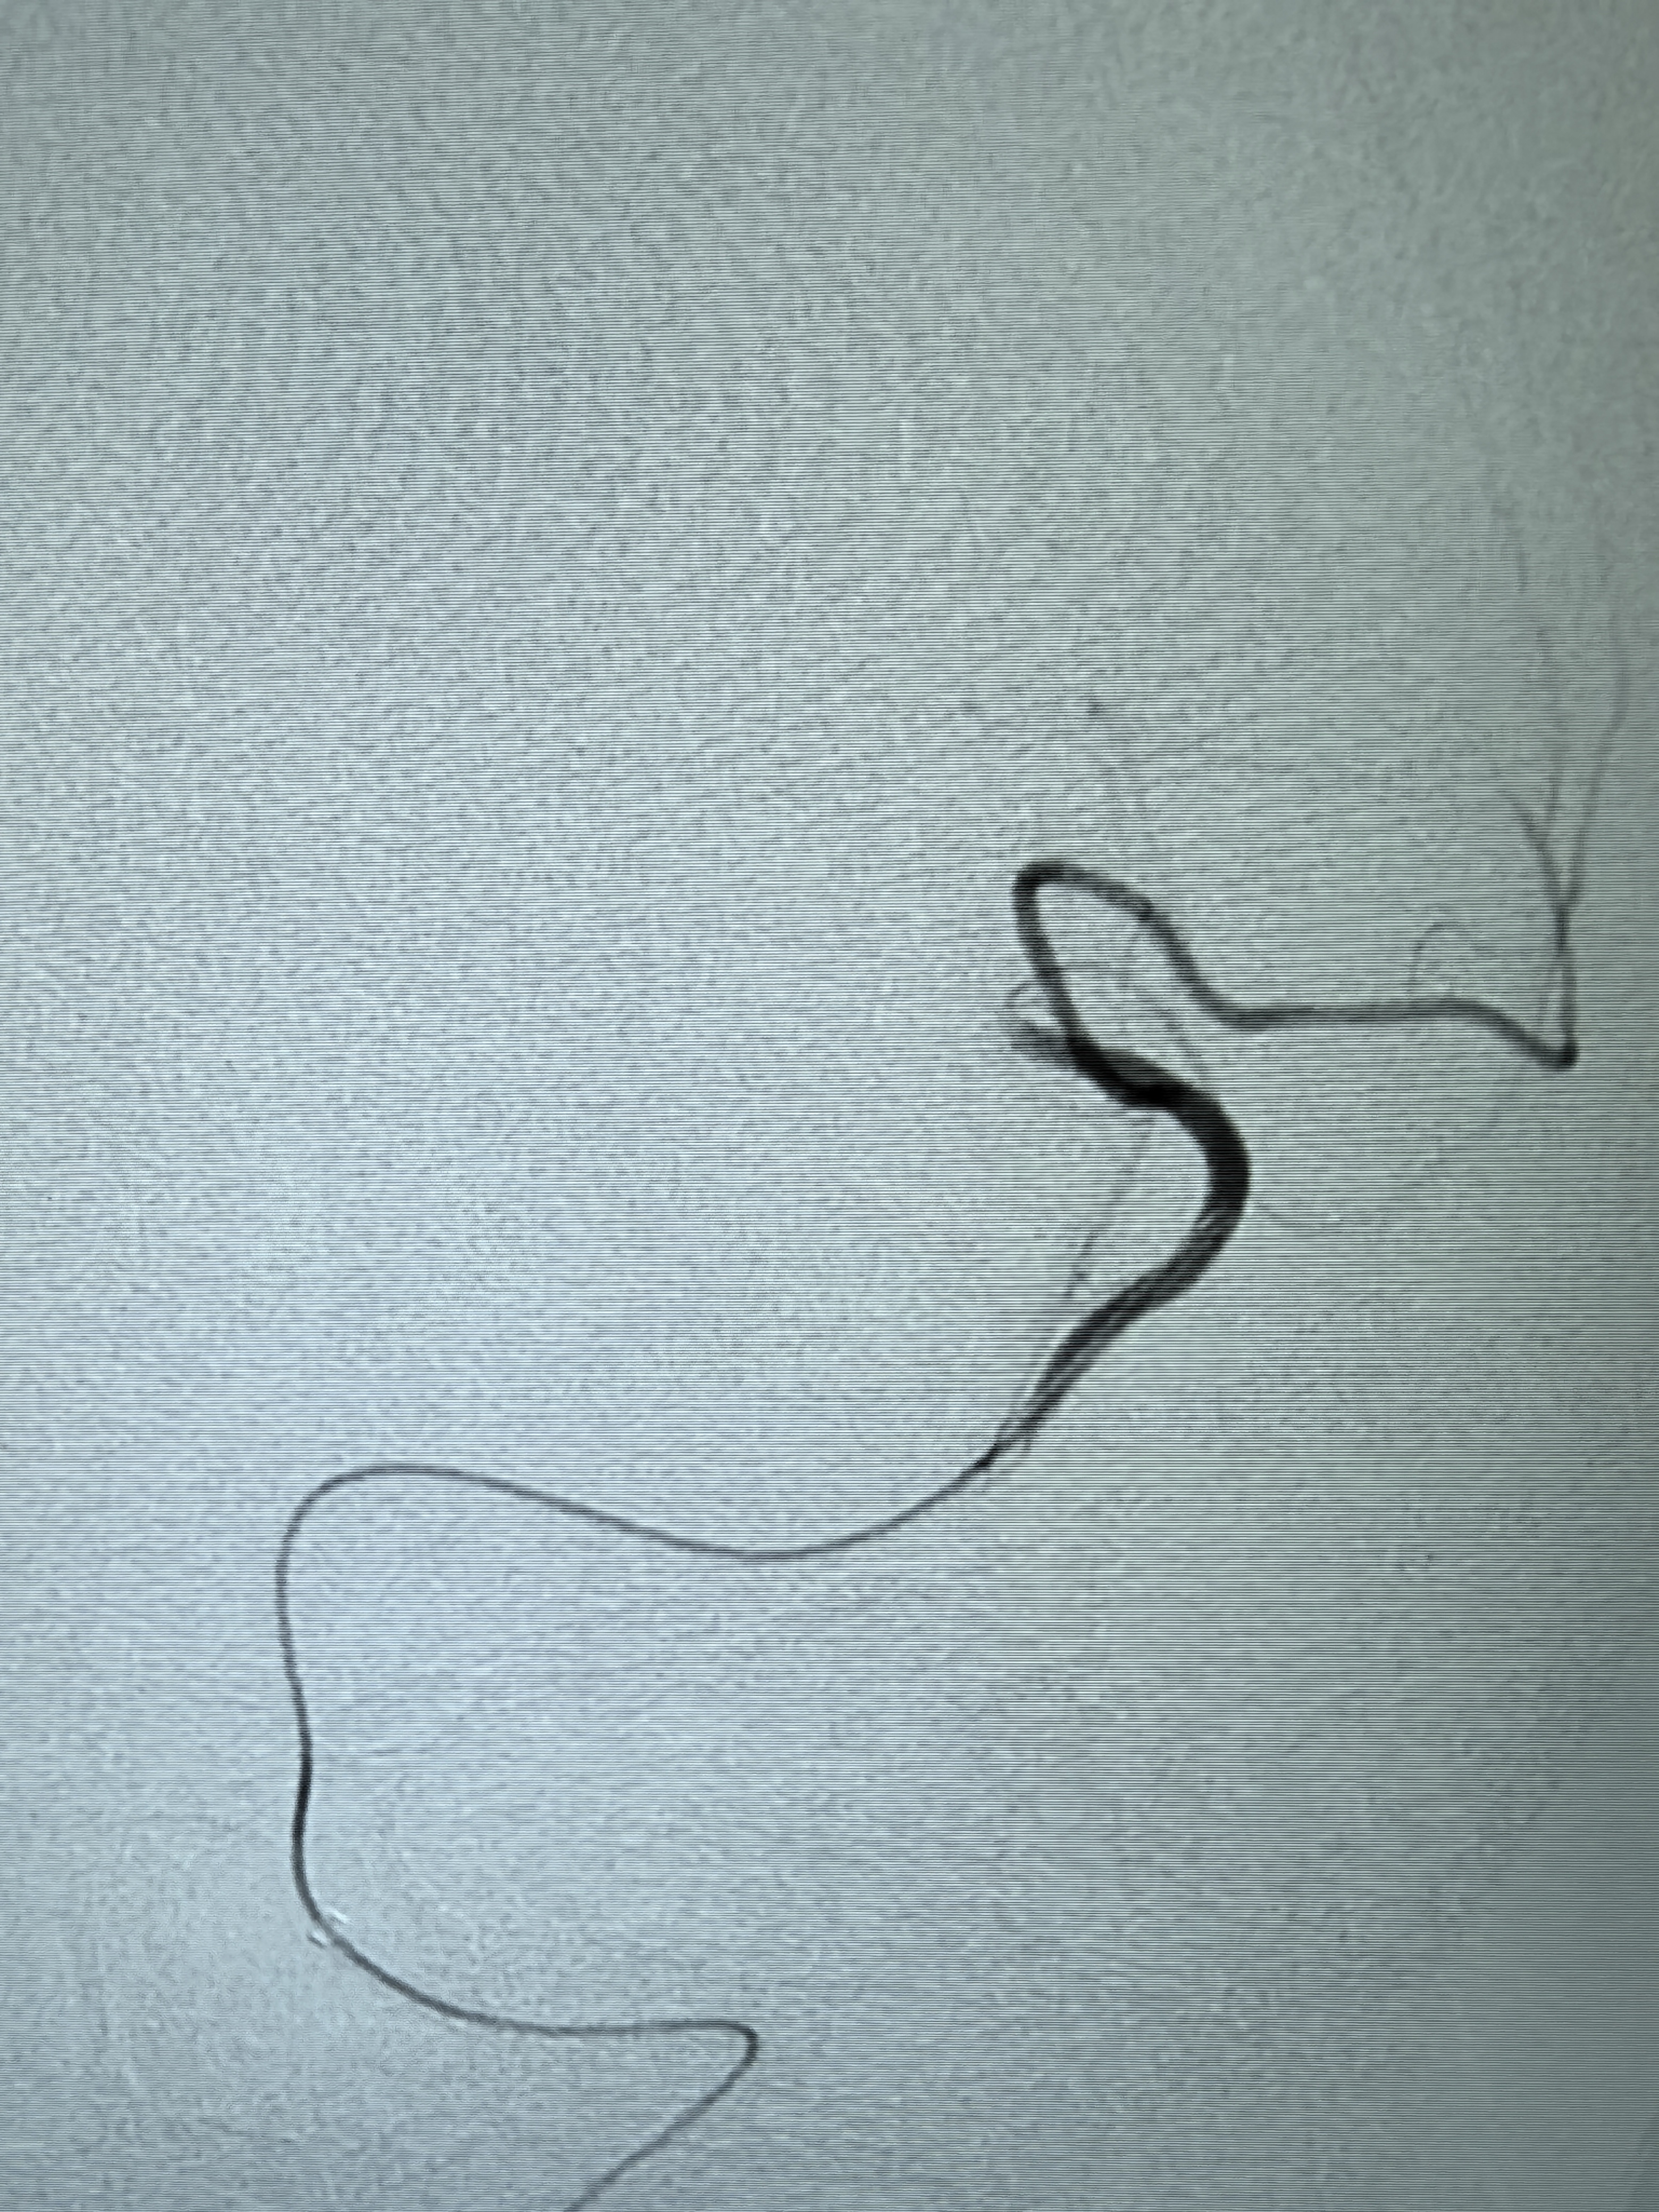

2、本例患者SWIM技术取栓一次后血管再通,颅内血流通畅。